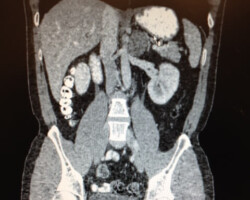

Dr. McCain, winner of the Pancreas Foundation Nobility in Science Award, has seen many pancreatic tumors and his practice. With his experience and expertise in this specialty small tumors of the ampulla are removed via a transduodenal approach while tumors of the head of the pancreas are resected using the Whipple procedure. We have recently seen a significant increase in solid and cystic tumors of the mid body and distal pancreas requiring less extensive resections for removal. Laparoscopy or robotic resection with intra-operative ultrasound is used to detect advanced disease at the start of each operation

Careful follow-up and medical oncology radiation oncology evaluation for pre or post operative treatment of pancreatic tumors is of great importance due to the high rate of recurrence / metastases of these tumors. There are multiple open clinical trials for this disease available